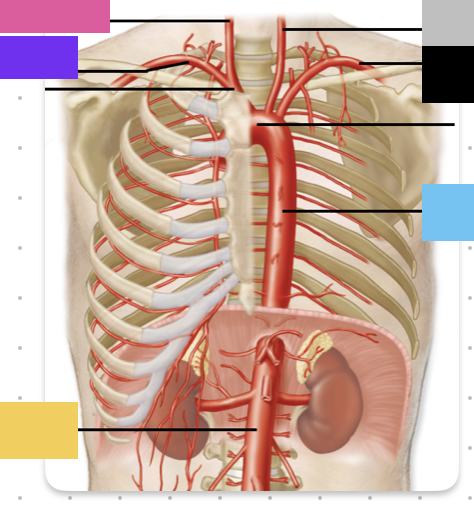

purple

left pulmonary artery

black

left pulmonary veins

blue

(branches of) right pulmonary artery

yellow

right pulmonary veins

orange

ascending aorta

purple

aortic arch

yellow

brachiocephalic trunk (blue)

pink

right common carotid artery

purple

right subclavian artery

red

left common carotid artery (grey)

green

left subclavian artery (black)

blue

descending aorta

blue

thoracic aorta

yellow

abdominal aorta